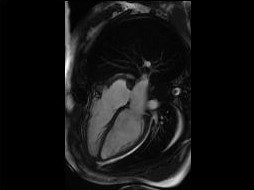

Shape instantiation which predicts the 3D shape of a dynamic target from one or more 2D images is important for real-time intra-operative navigation. Previously, a general shape instantiation framework was proposed with manual image segmentation to generate a 2D Statistical Shape Model (SSM) and with Kernel Partial Least Square Regression (KPLSR) to learn the relationship between the 2D and 3D SSM for 3D shape prediction. In this paper, the two-stage shape instantiation is improved to be one-stage. PointOutNet with 19 convolutional layers and three fully-connected layers is used as the network structure and Chamfer distance is used as the loss function to predict the 3D target point cloud from a single 2D image. With the proposed one-stage shape instantiation algorithm, a spontaneous image-to-point cloud training and inference can be achieved. A dataset from 27 Right Ventricle (RV) subjects, indicating 609 experiments, were used to validate the proposed one-stage shape instantiation algorithm. An average point cloud-to-point cloud (PC-to-PC) error of 1.72mm has been achieved, which is comparable to the PLSR-based (1.42mm) and KPLSR-based (1.31mm) two-stage shape instantiation algorithm.